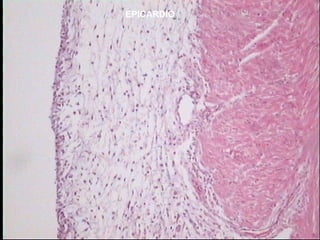

Pared cardiaca (3 capas)

-Epicardio : - capa fibrosa interna de tejido conectivo

- capa serosa externa o mesotelio ( capa

visceral del pericardio).

EPICARDIO